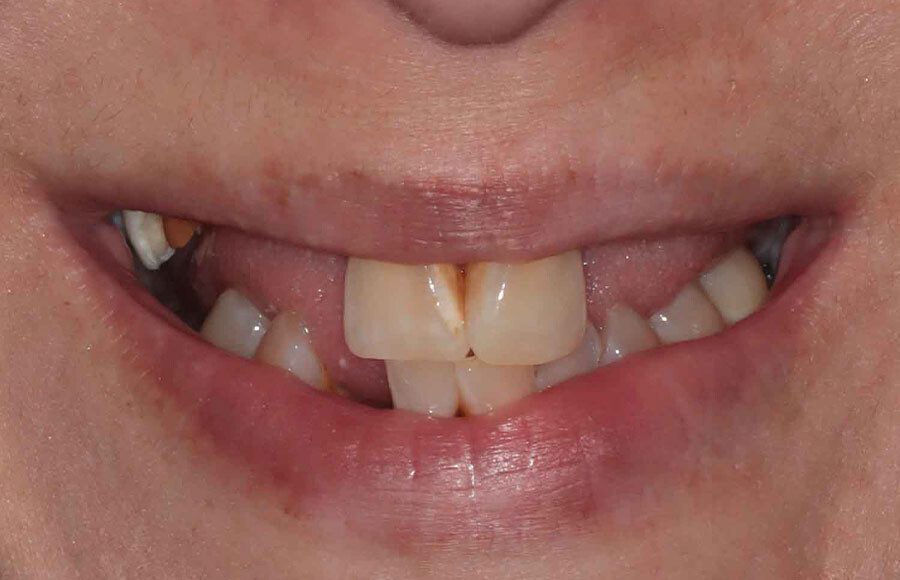

This patient came to our office dissatisfied with her smile. She a history of tooth decay/missing teeth and was looking to improve both her oral health and esthetics.